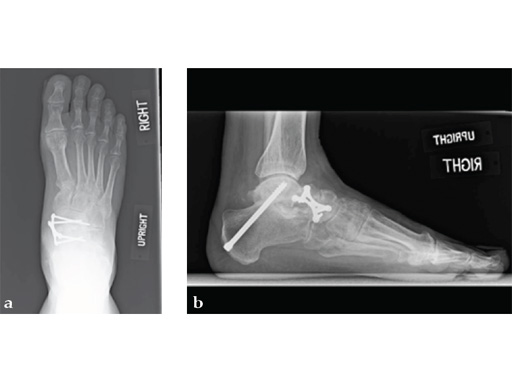

After 4 months the patient presented for a second opinion. His complaint was pain to the lateral column and subtalar joint. The preoperative lateral x-ray is notable for a malunited talar neck fracture with subluxation of the subtalar joint. The disproportion of the medial and lateral columns and a cavovarus position of the foot are seen on both the AP and lateral views. The degenerative changes at both the talonavicular and subtalar joints are significant.

The patient was treated with arthrodesis of the talonavicular and subtalar joints. The compression/ distraction device was used to restore the length of the medial column. The articular surface of the subtalar joint was prepared arthroscopically. The talonavicular joint was debrided then packed with a tricalcium matrix. Length was maintained using a locking X-plate. The subtalar joint was then fixed with a 6.5 mm headless compression screw.

The patient returned to work 3 months after surgery. He wears an ankle brace when on uneven surfaces. His lateral column and subtalar pain have resolved.